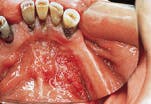

Oral cancer...

Intraoral SCC has a variety of clinical appearances. While the usual presentation is that of a chronic non-healing ulceration, intraoral SCC may also appear as an exophytic mass, or a red, white, or red and white plaque. Raised and firm borders may be present.

Intraoral SCC is typically asymptomatic; however, in some instances, pain and difficulty in swallowing may occur. Unlike SCC of the lip, metastasis is common and involves the regional lymph nodes.